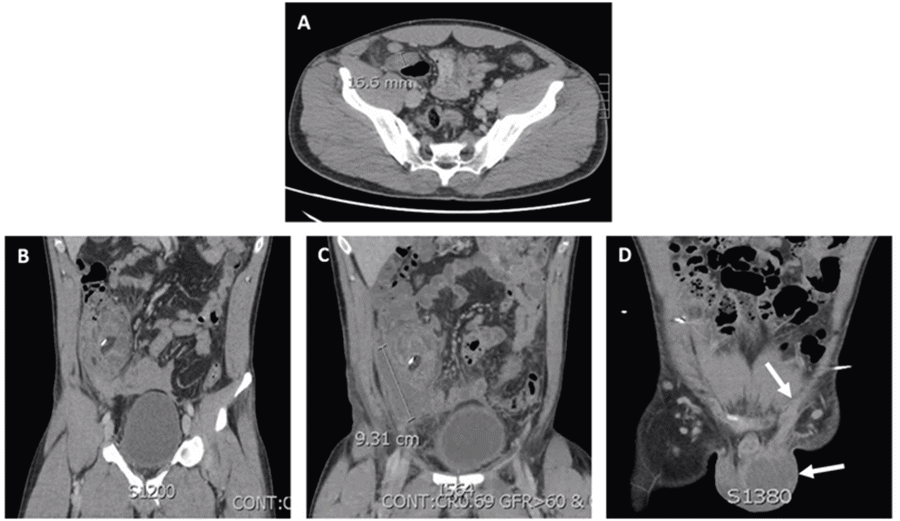

Figure 1. Abdominal CT Scans. Published with Permission

A) CT on initial admission for appendicitis showing dilated appendix to 16.6 mm with surrounding fat stranding and associated 1.1 cm appendicolith at appendiceal base; B) CT on POD5 demonstrating phlegmonous changes in right lower quadrant; (C) CT on POD 9 showing 4.9 × 3.0 × 9.3 cm rim-enhancing right lower abdominal quadrant abscess; and D) CT on POD 18 showing left scrotal abscess (bottom arrow) and enhancement of left spermatic cord (top arrow).

A 29-year-old healthy male presented to the emergency room with acute onset of right lower quadrant abdominal pain and nausea but no emesis. He reported that he experienced these symptoms for one day. His presentation did not include fever, chills, diarrhea, chest pain, or shortness of breath. He was afebrile with stable vitals, and his admission labs were notable for leukocytosis to 12.1. A subsequent abdominal CT scan demonstrated a dilated edematous appendix with an appendicolith at the appendiceal base (Figure 1A). The patient underwent an uncomplicated laparoscopic appendectomy, with findings of dilated, gangrenous, grossly non-perforated appendicitis. Some turbid fluid was present in the abdomen, but no free purulent fluid. The appendix was transected at the base with an Endo-GIA stapler, and a small amount of blood in the right lower quadrant was suctioned out. Perioperatively, the patient was placed on piperacillin-tazobactam (Zosyn). The patient had an uneventful postoperative course, he was advanced to a regular diet, and his bowel function returned. During his hospitalization, the patient developed mild swelling of his left scrotum with mild discomfort but no overlying skin changes, which was characterized as a reactive hydrocele, and the patient received non-operative management with scrotal support. He was then discharged home.

On postoperative day 5, the patient was re-admitted for recurrent right lower quadrant abdominal pain. A CT scan revealed a developing phlegmon in the right lower quadrant with retroperitoneal hematoma and a small hemoperitoneum (Figure 1B). A repeat CT scan performed on postoperative day 9 revealed an abscess in the right lower quadrant (Figure 1C). Two drains were placed in his right lower quadrant by interventional radiology (IR). During his hospitalization, the patient developed increased swelling of the left scrotum. A left scrotal ultrasound that was performed showed a complex hydrocele. Urology was consulted and recommended supportive care for this reactive hydrocele. During his hospitalization, he was treated with piperacillin-tazobactam (Zosyn) and discharged on a seven-day course of trimethoprim-sulfamethoxazole (Bactrim) after abscess cultures grew trimethoprim-sulfamethoxazole (Bactrim) sensitive E. coli but were negative for anaerobes.

On postoperative day 18, the patient presented again to the ED with increased left scrotal swelling and tenderness, but now, with fever, chills, and scrotal skin breakdown. CT scan showed the presence of a scrotal abscess and enhancement of the left spermatic cord (Figure 1D). The patient underwent scrotal incision, drainage, and wound vac placement by the urology service. He received treatment with piperacillin-tazobactam (Zosyn) until abscess cultures grew Bactrim-resistant E. coli primarily with light anaerobe growth (Bacteroides fragilis). He was discharged on a ten-day course of cephalexin and metronidazole. The patient underwent subsequent wound vac changes with urology until his wound was sufficiently healed. His IR drains were removed sequentially without issues. At the most recent follow-up, the patient had completed his antibiotics, had the wound vac and drains removed, and recovered normally without any further complications.